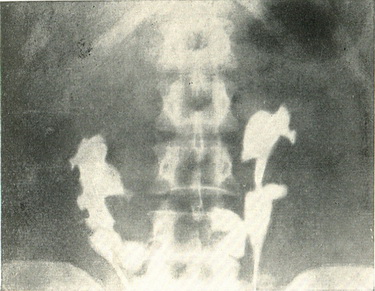

Точний діагноз може бути поставлений на підставі пієлографії, дає картину, характерну для дистопії обох нирок (рис. 54). Зображення самої нирки і перешийка виходить краще всього при пневморетроперитонеуме.

Рис. 54. Пієлограма підковоподібної нирки.